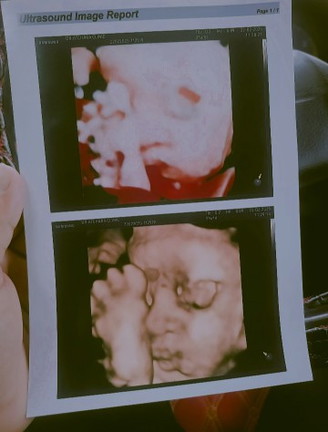

ได้31week1dayแม่ไปแอบส่องหน้ามา จมูกโด่งมาแต่ไกลเลย😂 อยากเห็นรูปอัลตร้าซาวด์ของแม่ๆจังอวดกันหน่อย

เอ็นดูความนอนหนุนเท้าลู้กกกกก

คุณหมอพยายามให้เอาลงแต่ลูกดื้อไม่ยอม55

บ้านนี้ดั้งหายไปไหนนนน🤣🥹🥰